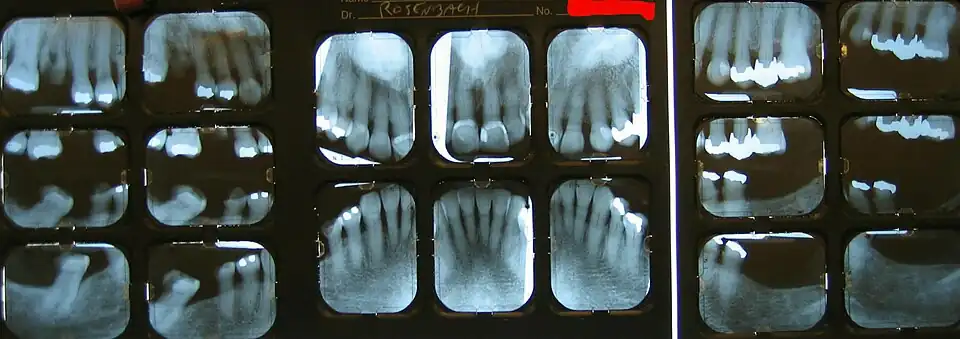

Röntgenstatus

Unter einem Röntgenstatus versteht man in der Zahnmedizin die Anfertigung von Einzelröntgenaufnahmen des Gesamtgebisses.

Die Darstellung aller zahntragenden Abschnitte des Ober- und Unterkiefers erfolgt durch eine Serie intraoraler Zahnaufnahmen. Die Aufnahmen können sowohl in analoger als auch in digitaler Form erfolgen. Die Vorteile gegenüber einem Orthopantomogramm (OPG) liegen in der hohen Detailerkennbarkeit der Einzelaufnahmen gegenüber dem OPG, der Vermeidung von Überprojektionen im Frontzahnbereich, von Verzerrungen und einer Vergrößerung der Abbildung.[1]

Der Röntgenstatus besteht aus 6 bis 14 Aufnahmen. Im Milchzahngebiss genügen sechs Aufnahmen, im Wechselgebiss zehn Aufnahmen. Im bleibenden Gebiss zehn bis vierzehn Aufnahmen, einschließlich sogenannter Flügelbissaufnahmen (engl.: Bite wing) zur Kariesdiagnostik.